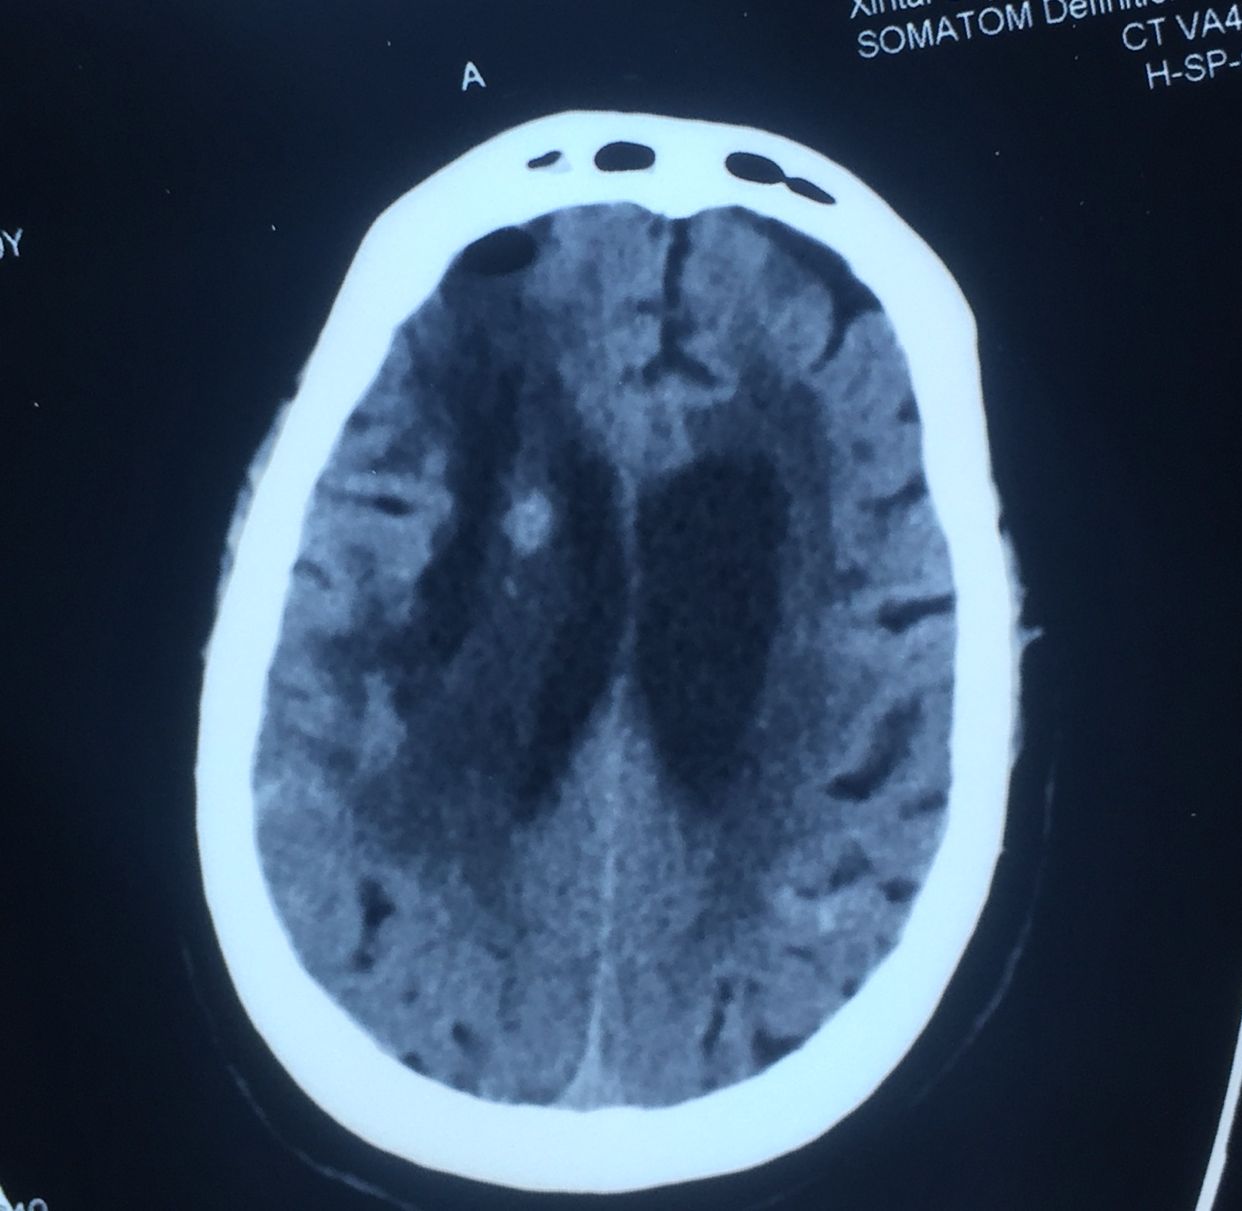

次日复查如上图:

出血未再增大。